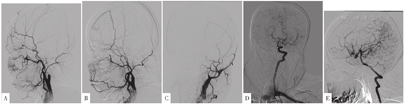

2017-11-16,患者因"大小便失禁1 d"而再次入住滨州医学院附属医院(距离上次住院时间为2年9个月)。患者入院前1 d无明显诱因出现大小便失禁,无肢体活动障碍及言语不清,为求系统诊疗而就诊于滨州医学院附属医院,门诊以"大小便失禁"收入院。查体:血压为129/63 mm Hg,心率为83次/min,意识清,言语流利,甲状腺Ⅱ度肿大、质软、无结节感、无压痛,NIHSS评分为0分。颅脑MRI检查结果:右侧大脑半球软化灶形成,左侧额叶急性脑梗死灶。头颈部MRA检查结果:右侧颈内动脉、右侧大脑前动脉、右侧大脑中动脉未见明显显影,考虑狭窄、闭塞;左侧颈内动脉起始段粥样硬化斑块形成,远端管腔狭窄(见图2),建议行头颈部CT血管造影(CTA)或数字减影血管造影(DSA)。甲状腺超声检查结果:甲状腺弥漫性增大,血流较丰富,流速增高,符合甲状腺功能亢进症表现;甲状腺双叶低回声结节。甲状腺功能指标:游离三碘甲状腺原氨酸为46.43 pmol/L,游离甲状腺素>100 pmol/L,促甲状腺激素<0.005 mU/L,抗甲状腺球蛋白抗体为1 051.0 U/ml,甲状腺过氧化物酶抗体为180.7 U/ml。既往史:脑梗死、高血压病史2年,否认糖尿病病史。

注:A~D为颅脑DWI,示左侧额叶团片状高信号影(考虑为脑梗死);E~F为颅脑磁共振成像(MRI),示右侧大脑半球软化灶形成;G~H为头颈部MRA,示右侧颈内动脉、右侧大脑前动脉、右侧大脑中动脉未见明显显影(考虑狭窄、闭塞),左侧颈内动脉远端管腔狭窄